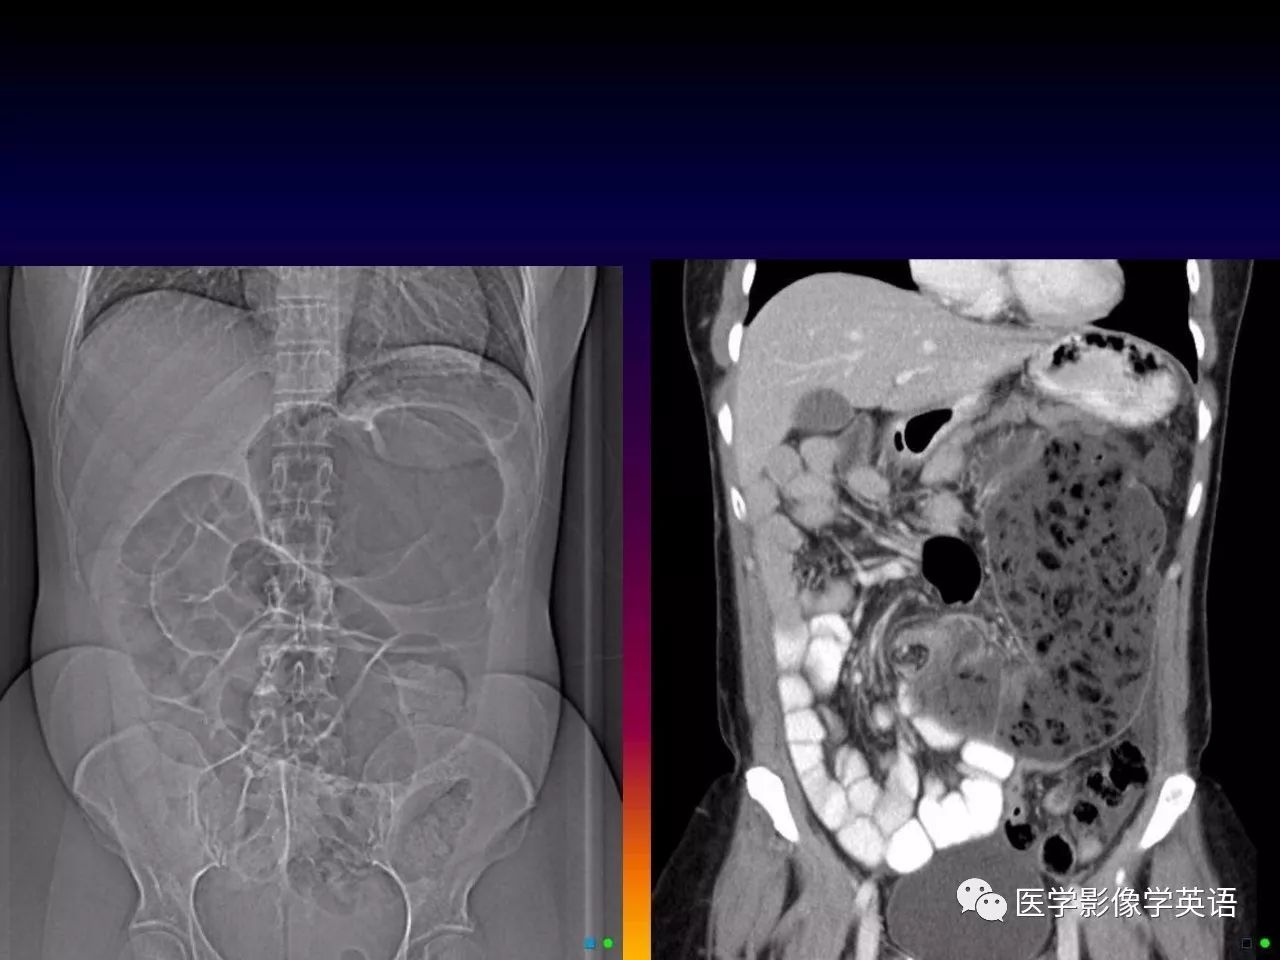

82. Mid-gut volvulus (malrotation)

83. Mid-gut volvulus (malrotation)

84. Mid-gut volvulus (swirl sign)